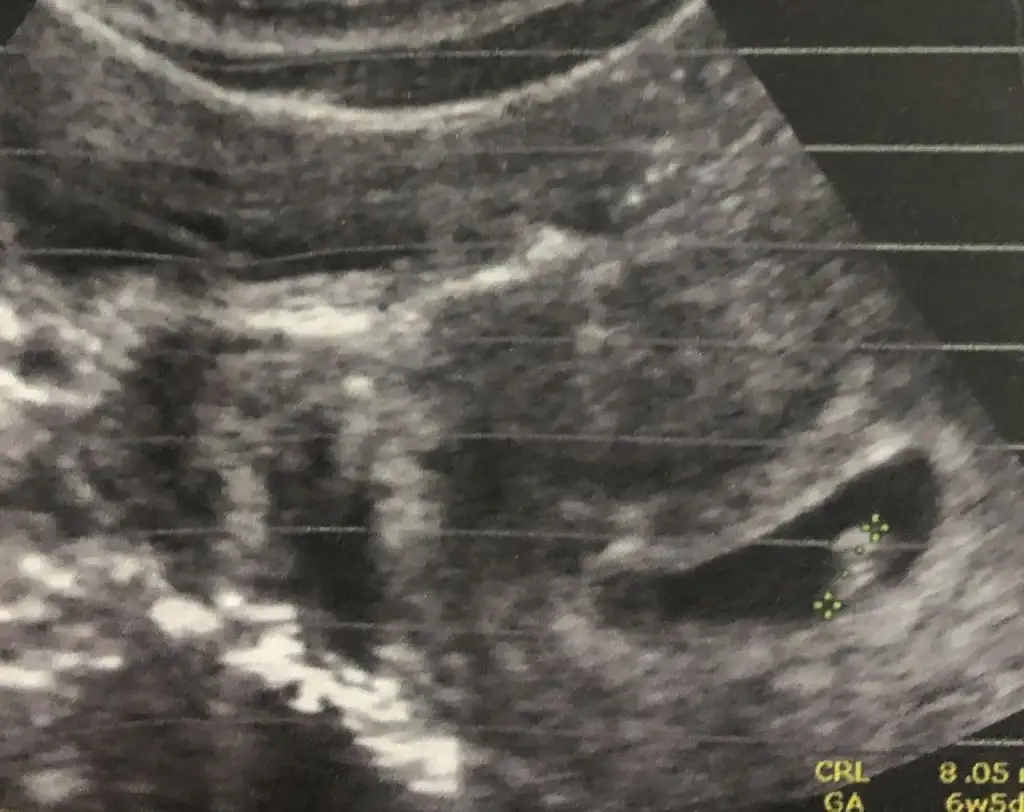

Ayy zor gördüm uste dr + getirmiş karından ise az saga yakın kızEki Görüntüle 2597649 budami olmaz

Erkek buna göre siz yinede nub için 11 yada 12 hafta usg paylaşın